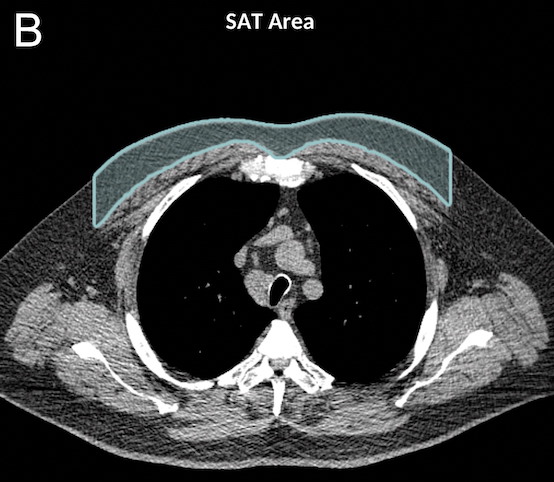

La tomodensitométrie (TDM) thoracique est souvent utilisée pour caractériser la BPCO, dépister le cancer du poumon ou planifier des options chirurgicales. Mais elle offre désormais l'opportunité d'évaluer l'obésité et la sarcopénie grâce à des biomarqueurs des tissus mous.

Pour la nouvelle étude, le Pr Bluemke, avec les Drs Farhad Pishgar et Shadpour Demehri, de la Johns Hopkins School of Medicine, et leurs collègues ont utilisé des examens de TDM thoracique pour étudier les associations entre les marqueurs des tissus mous dérivés de l'imagerie et la mortalité toutes causes confondues dans la BPCO. Le groupe d'étude était composé de 2994 participants issus de l'étude multi-ethnique de l'athérosclérose (MESA), une recherche examinant les rôles des marqueurs des tissus mous et osseux dérivés de l'imagerie pour prédire les résultats pertinents pour les maladies cardiopulmonaires. Sur les 265 patients du groupe d'étude atteints de BPCO, 49 (18%) sont décédés au cours de la période de suivi.

Une plus grande quantité de graisse intermusculaire était associée à des taux de mortalité plus élevés. Les recherches existantes ont lié des niveaux plus élevés de graisse intermusculaire au diabète et à la résistance à l'insuline. Un tissu adipeux sous-cutané plus élevé, en revanche, était lié à des risques plus faibles de mortalité, toutes causes confondues. Les auteurs ont montré de manière convaincante que la graisse dans le muscle était beaucoup plus prédictive de mauvais résultats qu'une simple distribution de graisse sous-cutanée.